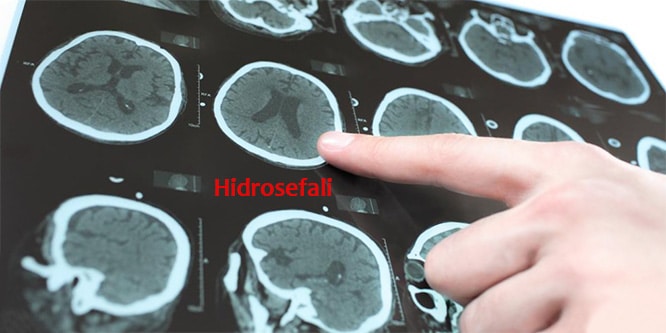

Beyin tümörü uyku hali. Yetişkinlerde ikincil beyin tümörleri birincil beyin tümörlerinden çok daha yaygındır. Ancak şikayetler çok daha çeşitlilik gösterebilir. 1925 yılından beri bilinen bu beyincik tümörü çok ayrı hücresel ve klinik özellikeri olan ve oldukça habis karekterli bir beyincik tümör tipidir beyinciğin çocuklarda en sık tümörü olup tüm primer beyin tümörlerininin 4 10 teşkil ederler. Patoloji alındı ondada tam teşhis konulmadı.

Sürekli uyku hali i̇çin hangi doktora gidilmeli. Eşim iki ay önce beyin tümörü teşhisi kondu. çekilen emar ve tomografi sonucuna göre tümör dendi. Bu şikayetler beyin tümörü belirtisi olabilir.

Uykuyu kontrol eden sinirler beyin sisteminde yer aldığı için sürekli uyku problemini çözmek için nöroloji bölümüne gitmeniz gereklidir. İkincil beyin tümörleri en sık kanser öyküsü olan kişilerde görülür. Denge kaybı uyku hali gözde görme sorunları duyma sorunları el ya da ayaklarda his sorunları ruhsal değişiklikler halüsinasyonlar görebilir yemek yeme sorunları yutkunma sorunları yemek yeme sorunları halsizlik trombosit düşüklüğü lökosit. Sadece uyku hali be yorgunluğu vardı.

Nöbet geçirmesi şimdiye kadar olmadı. Uyku apnesi bulunanların kalp damar hastalıklarına ve beyin damar hastalıklarına inme gibi yakalanma riski daha yüksektir. Ancak baş ağrısı bazen beyin tümörü beyin kanaması ve anevrizma gibi yaşamı tehdit eden. Ancak nadir durumlarda metastatik beyin tümörü vücudunuzun başka yerlerinde başlayan kanserin ilk belirtisi olabilir.